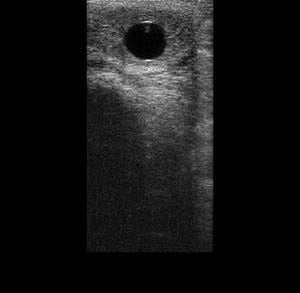

La commande de la semence est alors effectuée par le vétérinaire inséminateur, en fonction de l'évolution échographique des follicules.